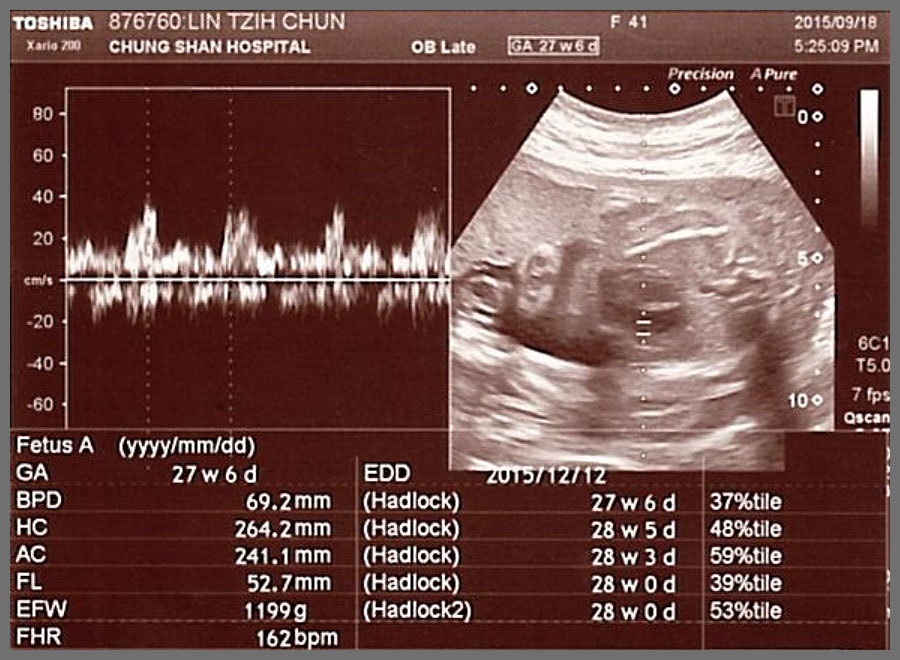

林姿君懷孕28周回診時,胎兒心臟的白點已消失

在第28週到醫院檢查,當天超音波大概照了約30分鐘,等於超音波檢查又完整做了一遍,當天檢驗師幫胎兒全身的每一個地方都拍得很澈底,尤其是心臟的部分,她看了很久,檢驗師才跟我們說,胎兒心臟的白點並沒有看到,心臟的白點確定已經消失了,我們當下跟檢驗師說這是因為有尊貴的金剛上師 仁欽多吉仁波切的加持,胎兒才能從22週拍到心臟有2個白點,到28週心臟白點完全消失,真的太不可思議了,這一切都要感恩尊貴的金剛上師 仁欽多吉仁波切。